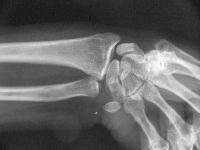

Palmar flexion of the scaphoid, lunate dorsiflexion.

Scapholunate diastasis.

Click for larger image